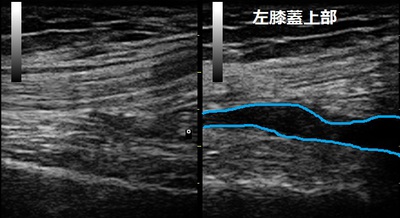

坂戸市 インストラクター 膝関節の痛み 「水が貯まっているの!?」

右膝上部 左膝上部

坂戸市 女性スポーツインストラクター 左膝関節に痛み 膝関節水腫。

仕事以外にも趣味でフルマラソンやトレイルランの大会に出場するために毎日、ランニングしています。4か月前に

ランニング中に転びそうになってから左膝に痛みを感じるようになりました。

膝関節周囲の筋肉が弱っていると思い、少々痛くてもマシーンを使ってウェイトトレーニングなどの運動療法で

膝の痛みを克服しようと思っていました。5日前にランニング中、転んで左膝を地面にぶつけてしまい、膝が腫れて

しまいました。

超音波検査では左膝関節に関節液(血腫含む)が過剰に溜まっていることが認められました。当院で関節液の

吸収を高める治療器を使用します。長い間、痛くて膝関節を深く曲げなかったせいで関節や大腿四頭筋が硬く

拘縮してしまったので、筋肉の柔軟性を高めながら関節の可動域を広げていきます。

日常生活ではランニングは暫く休止します。インストラクターの仕事は可能な範囲で行い、テーピングではなく

しっかり膝を固定できるサポーターを装着しました。